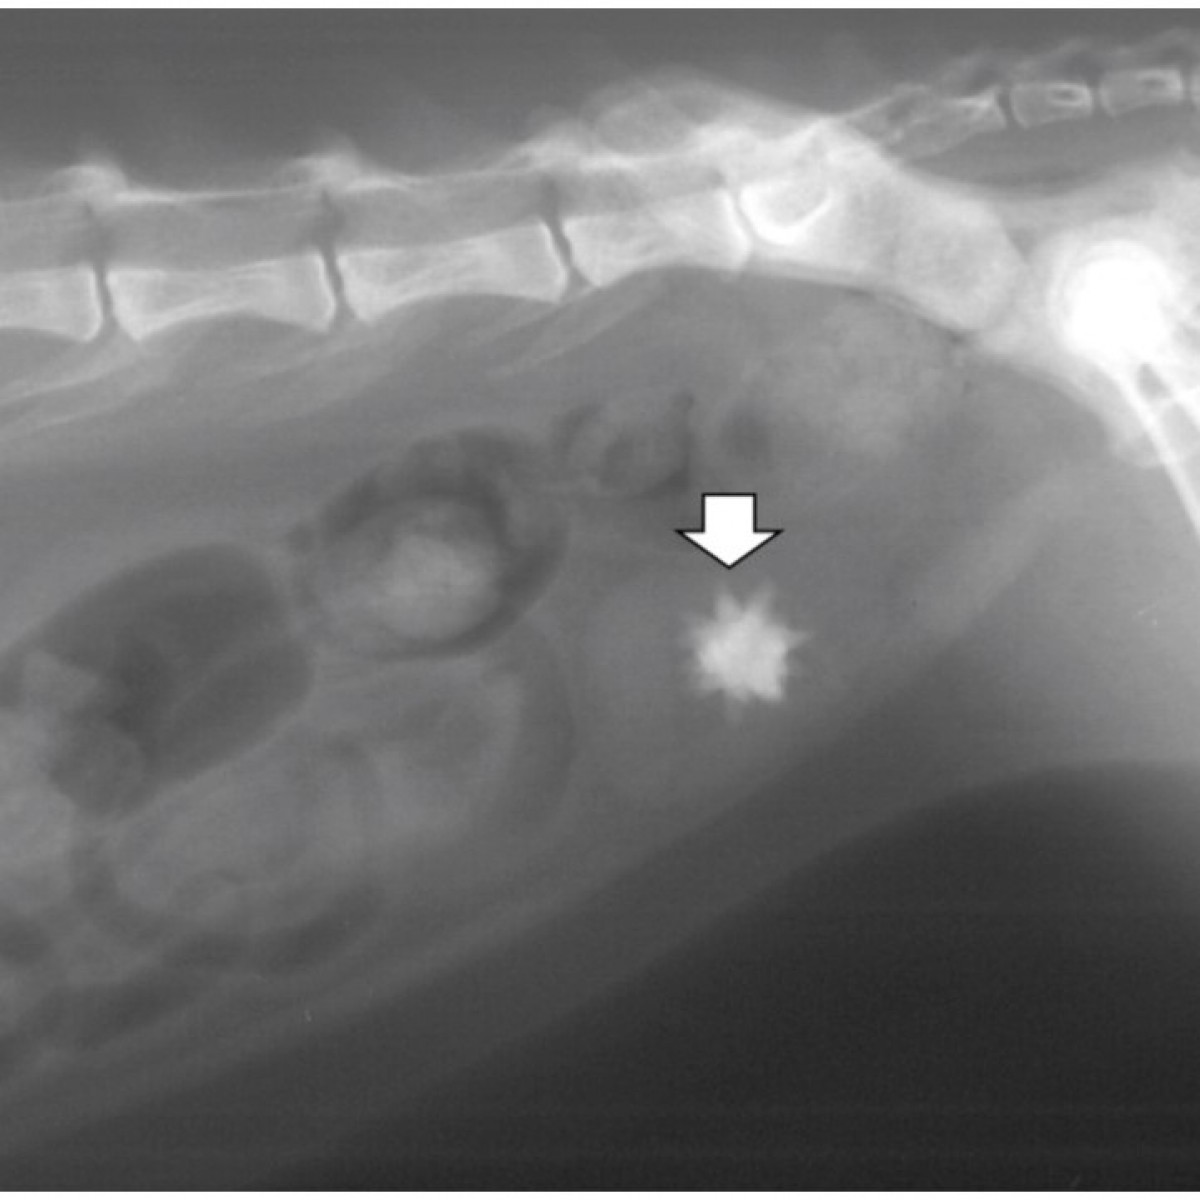

Uroliths occur commonly in the bladder and/or urethra of cats and can be lifethreatening if urethral obstruction occurs. Calcium oxalate accounts for 40–50% of urocystoliths and these stones are not amenable to medical dissolution; therefore, removal by surgery or minimally invasive techniques is required if uroliths must be treated. Medical protocols for prevention involve decreasing urine saturation for minerals that form uroliths.